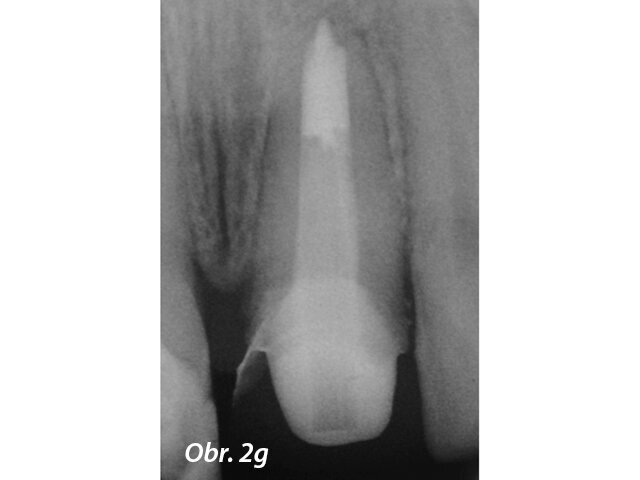

Apexifikace

Aby se zabránilo přetlačení výplňového materiálu u zubů s nedokončeným vývojem, používá se MTA jako apikální zátka. Výsledky mnoha studií ukazují, že MTA podporuje tvorbu tvrdých tkání více a je spojeno s menším počtem zánětlivých reakcí než jiné testované materiály (Simon a spol. 2007) (obr. 2a–g).

Endodonticky ošetřený zub s píštělí

Po reendodoncii se ukázal otevřený apex

Aplikace PD MTA White s MAP systémem

Kondenzace MTA papírovým čepem

Postoperační RTG ukazuje výplň MTA a rekonstrukci se světlovodným čepem